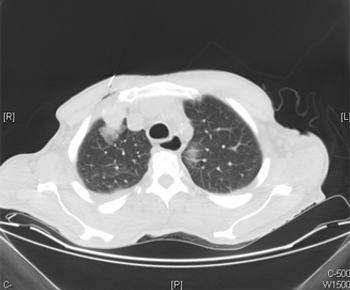

A 71-year-old woman presented with back pain and was incidentally found to have a left upper pole renal mass. She underwent left open partial nephrectomy; the pathology results revealed a 2.2-cm clear-cell renal cell carcinoma (RCC) with negative margins and a Fuhrman nuclear grade of 2.